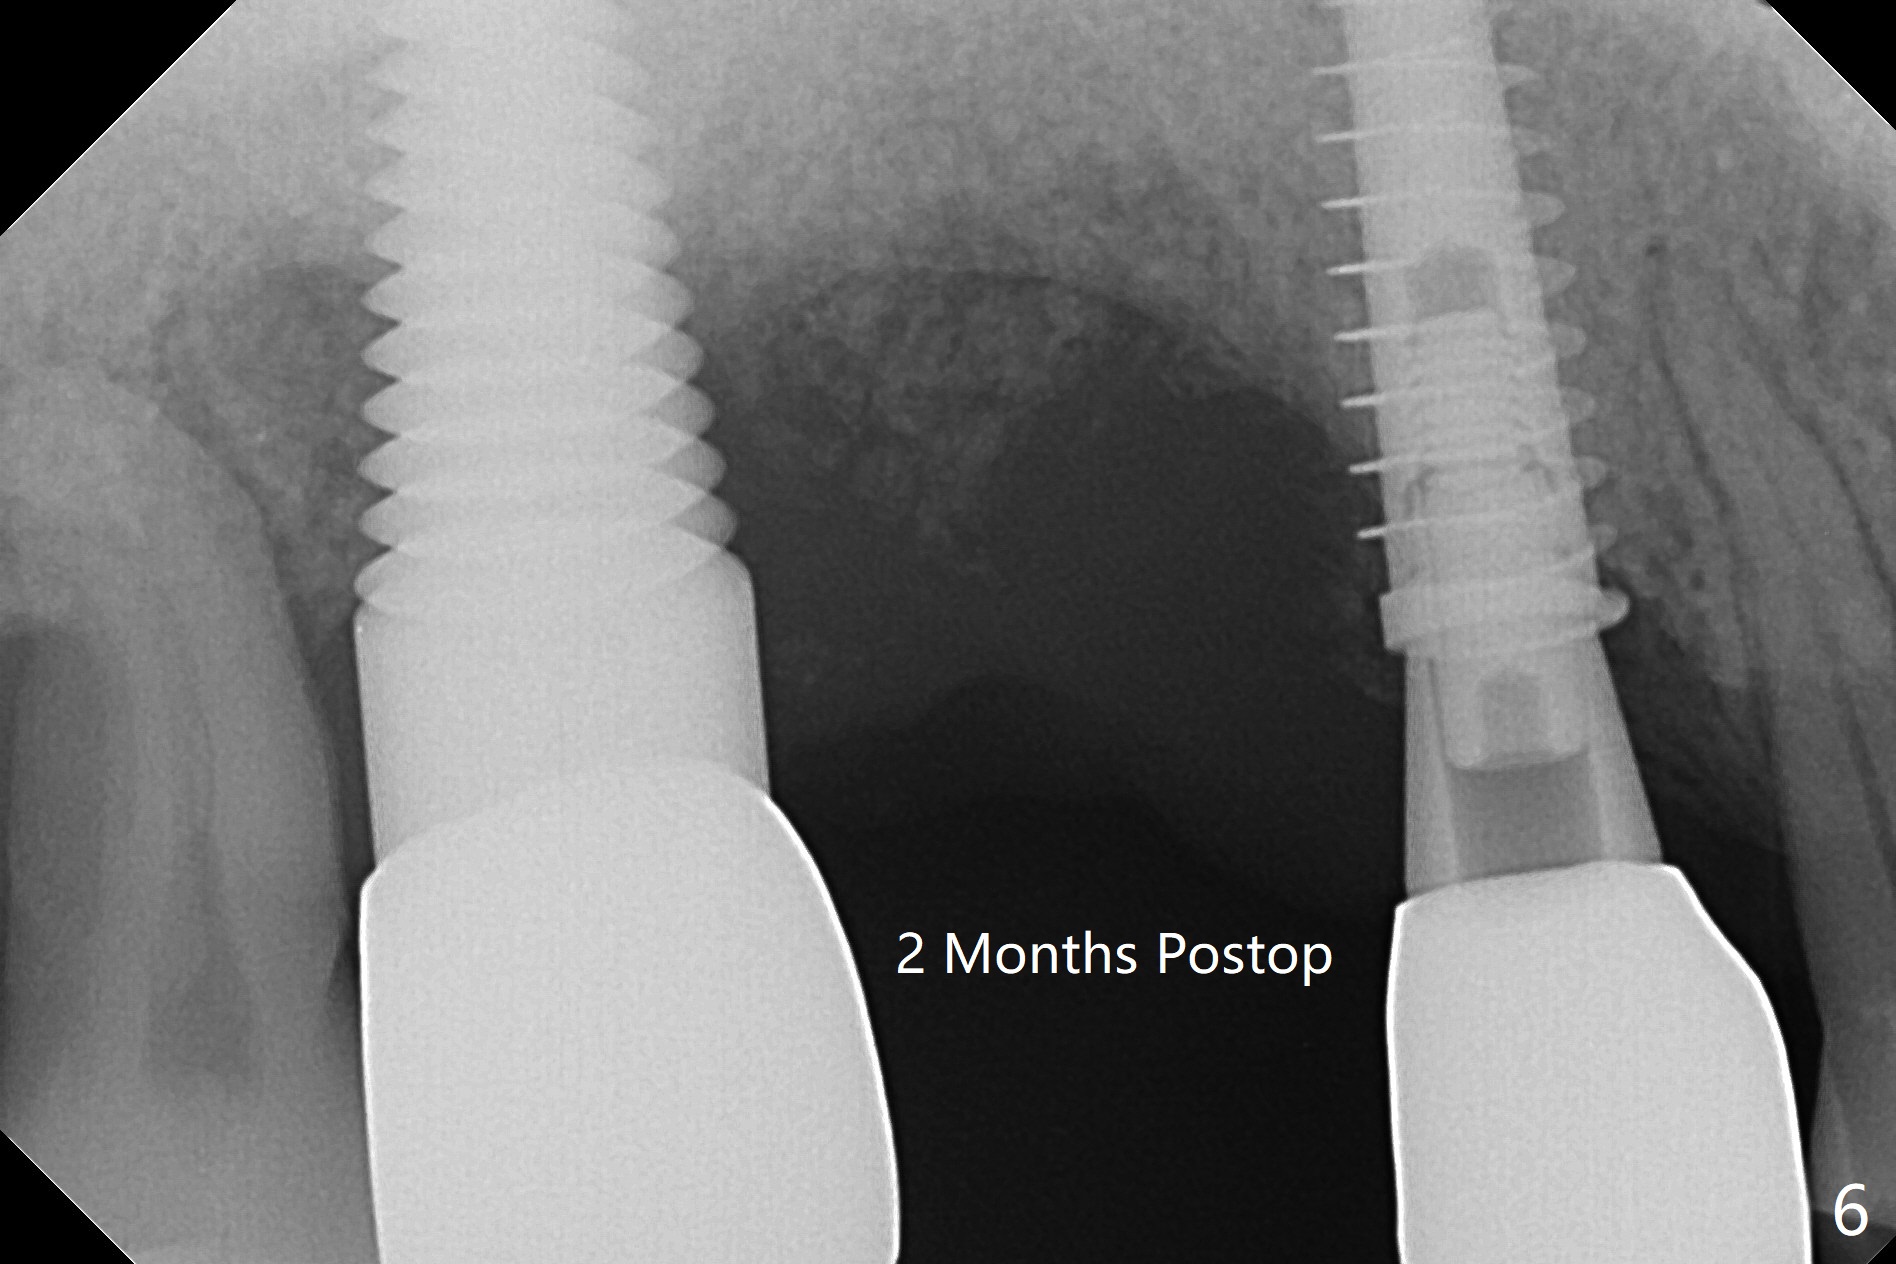

51岁男(牙周炎,咀嚼力大),右上6植体(7x17毫米,即刻种植,当时牙槽窝大,使用大植体,减少骨粉量)使用6年10月后松动,在诊所用手指取出,颊侧牙龈低,刮拔肉芽组织时发现颊侧,腭侧骨壁都缺失,但是没有通入上颌窦,植入粘性骨粉(Vanilla),覆盖一张PRF膜,4-0PGA缝线尽量严密缝合(图一,让口子骨粉有充分血供,相应减少角化龈和骨质高度),然后使用树脂敷料固定(PRF膜很快吸收)。7植体近中螺纹暴露,钛刷清洗后,骨粉放置于表面,而5远中深部螺纹好像暴露,浅部却被牙龈(乳头处)覆盖,所以骨粉无法进入缺失地方(图一:*)。理想的话,应该将牙龈分离(图二:弯箭头),这样骨粉就能进入缺损区域。6愈合后植牙时,用类似方法植骨。术后一周局部卫生好,没有任何不适(图三)。当术后五周树脂敷料取出时,骨粉好像生长不好(图四)。术后两个月伤口愈合(图五),但是骨粉失去不少(图六)。Return to No Caries Xin Wei, DDS, PhD, MS 1st edition 02/09/2021, last revision 08/09/2021